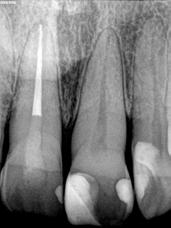

A mikrotöltésű kompozitok röntgenelnyelőek, különösen a mikrohíddal (13. ábra) összehasonlítva, amely a röntgenfelvételeken diagnosztikai problémát jelenthet, különösen az interproximális területeken. Mivel eredendően gyengék, a mikrotöltelékeket nem szabad olyan területekre helyezni, amelyek okklusális terhelésnek lesznek kitéve (6. ábra). Csak kis mennyiséget kell használni, az okklusális terhelés a sokkal erősebb mikrohibrid kompozitra marad.

A fogakat nehéz latexmentes gumidámmal (Isodam, 4D Rubber) izolálták. A meglévő kompozitot eltávolítottuk; egy kromatikus mikrotöltésű kompozitot helyeztünk fel, és egy fehér színt (Creating Color, Cosmedent) vittünk fel egy #8-as K-résszel, vízszintes mozgással, hogy a vízszintes mintázatot lemásoljuk (5. ábra), ezután egy akromatikus mikrotöltésű kompozitot adtak hozzá. A 6. ábra az azonnali posztoperatív eredményt mutatja, a 7. ábra pedig a négyéves utóvizsgálatot, amely a mikrotöltött kompozit megmaradt fényét mutatja.